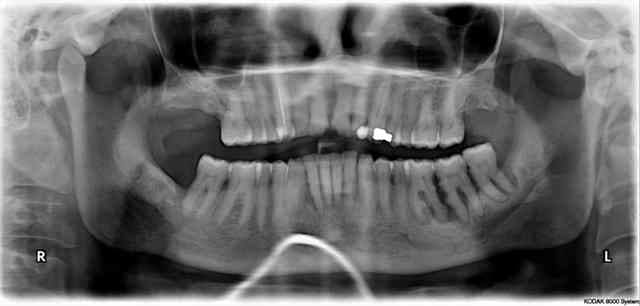

Paro aggressive généralisée. Patiente en traitement initial causal. Instruction + depuration/rotscaling.

Radio initiale de 43 :

Radio de cicatrisation lors de l'évaluation à + 6 mois.

Aucune chirurgie régénerative. Juste depuration/rotscaling et maintenance !! :